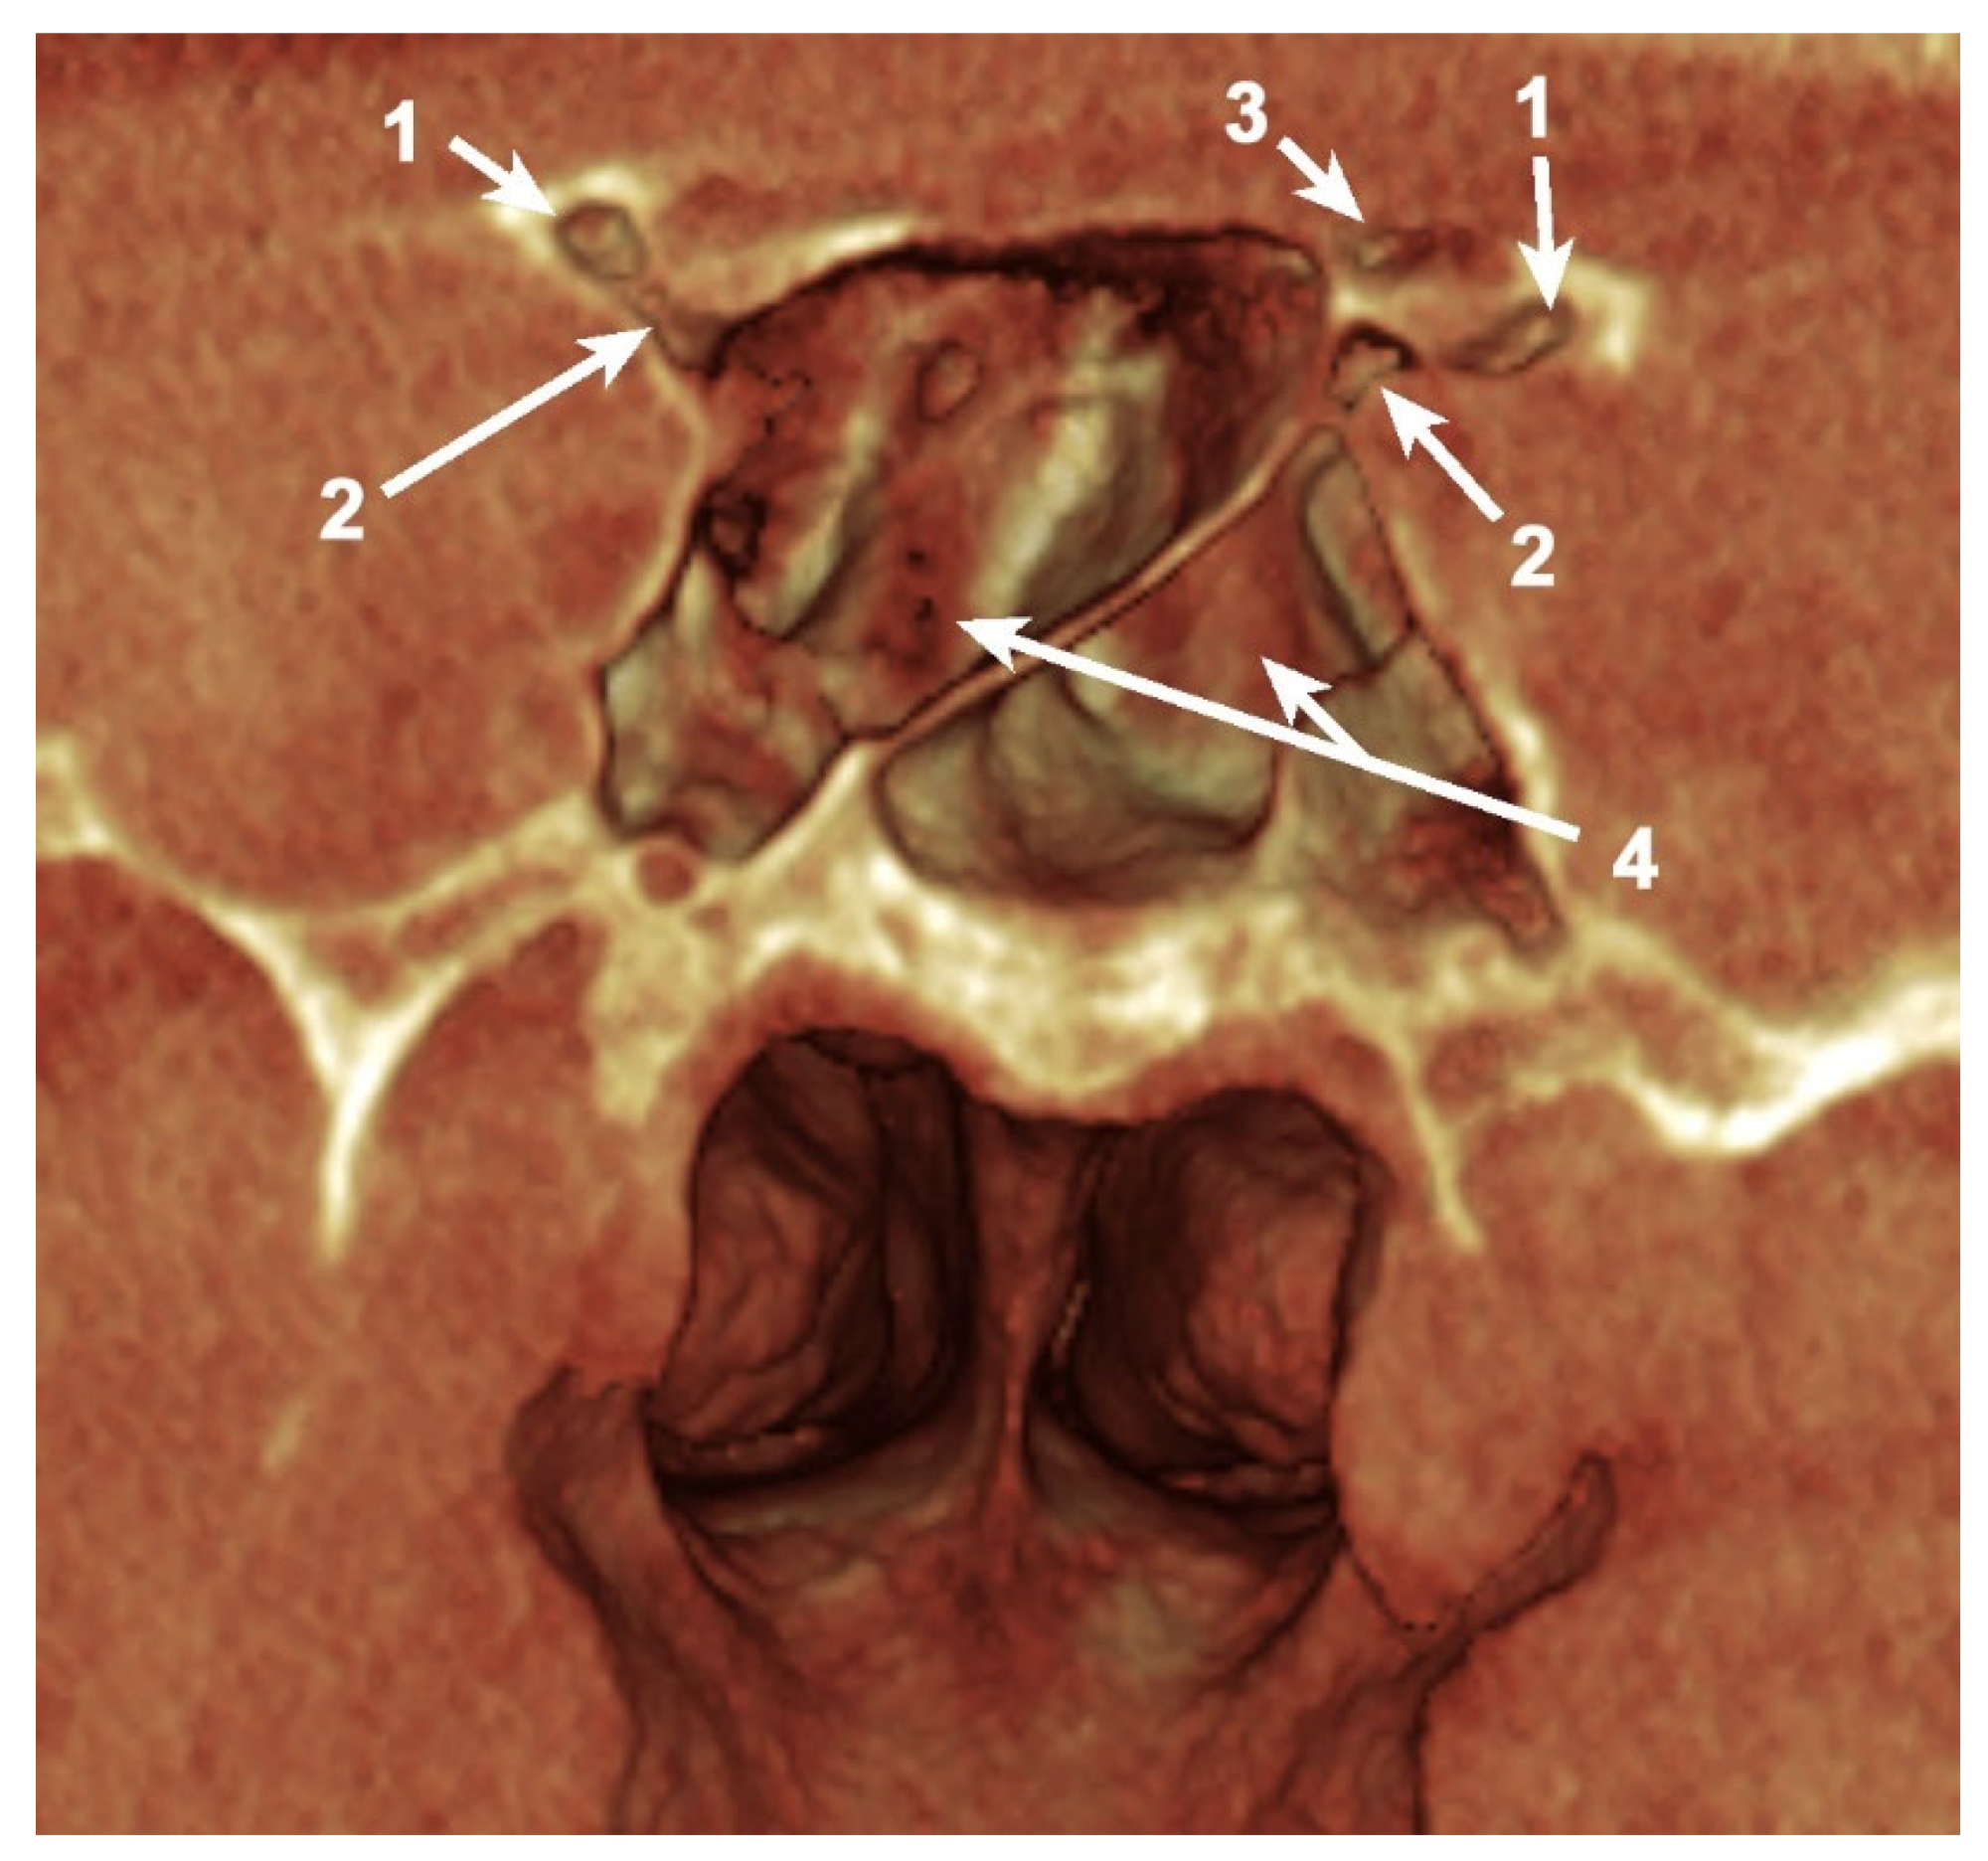

Figure 2. Coronal, bilateral three-dimensional volume rendering of the anterior clinoid process (ACP) and sphenoid sinus, posterior view. 1. Pneumatized ACP; 2. Pneumatized optic strut; 3. Pneumatized anterior root; 4. Sphenoid sinus.

Simultaneous pneumatization of both LSW roots was noted in 31 cases (38.75%) and 43 sides (26.87%) (Table 2; Figure 3). This kind of extensive pneumatization was more frequent in the female group (22 cases, 71%).

Five (16.13%) out of the 31 cases with pneumatization of both LSW roots presented combined pneumatization. If, for the other cases, the origin came either from PEAC (non-ONC/ ONC) or the sphenoid sinus, in these 5 cases, the simultaneous pneumatization occurred from separated origins for each of the two (Figure 3). Two of these patients presented the ONC extending into the OS and the sphenoidal sinus within AR, and the other three cases presented ONC pneumatization extended within the AR and the sphenoidal sinus with a recess within the OS.